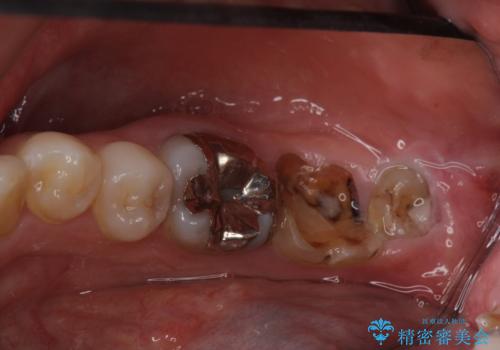

- 銀の詰め物が気になるとのことで来院。

2本隣り合っているつめものを、同時にやりかえをしました。

- 14万円(左下5・左下6 emaxプレスインレー 7万円 x 2)費用は治療当時の料金となります

向かい合う銀歯を同時にやり変えることで、コンタクト(歯と歯の間の形)を理想的に仕上げることができ、ものも挟まりにくいように仕上げることができます。